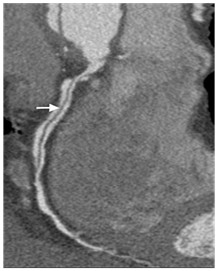

Cardiac computed tomography (CT) demonstrated patent left coronary arteries, a massive dissection flap extending from beyound the arortic graft to involve the descending aorta and a right coronary artery (RCA) dissection extending from the origin to the distal segment of RCA (Figure 4 & 5). The coronary dissection was not flow limiting and there was no evidence of obstructive coronary artery disease. The aorto-right ventricular fistula (ARV fistula) was detected by CT as a small defect four millimeters in size between the aorta and right ventricle (Figure 6).

Figure 4 Curved MPR image demonstrates the dissection flap in RCA(arrow), ascending aorta graft (*) and the residual dissection flaps in the aortic arch and descending thoracic aorta.

Figure 5 Curved MPR image demonstrates right coronary artery dissection (arrow).